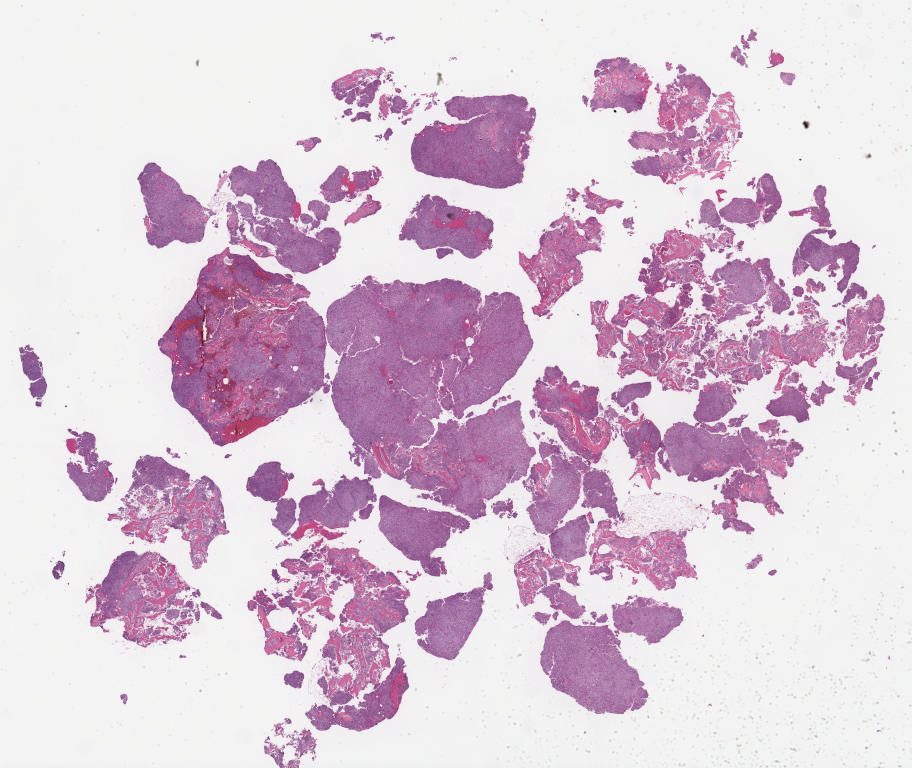

Case2-.svs

93624

x

88372

@

40X